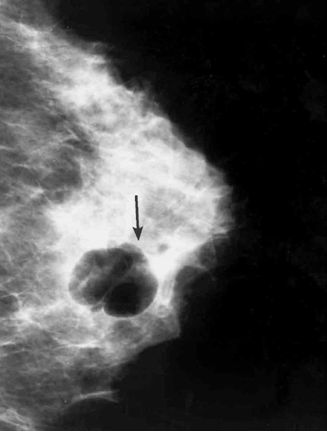

מכשיר העל-שמע (אולטרה-סאונד) מאפשר להבדיל בין כיסיות לבין גוש סולידי (תצלום 13.12). לאחר אבחון הכיסית אפשר לנקרה, להזריק לתוכה אוויר ולהדגים היטב את דפנותיה (תצלום 14.12).